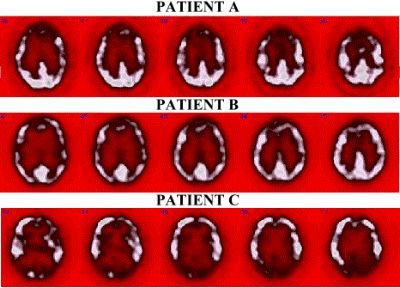

Q.     Explain the images at the top please.

First, this unusual color scale is chosen to accentuate the gray matter. Patient A demonstrates diffuse frontal hypometabolism due to a head injury. In comparison, Patient B demonstrates only mild right frontal hypometabolism, also due to head trauma. Patient C presents with dementia and demonstrates diffuse hypometabolism in the posterior occipito-parietal regions and mild hypometabolism in the temporal and frontal regions.